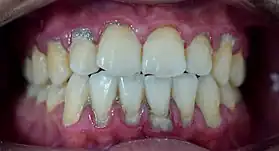

Calculus formation is associated with a number of clinical manifestations, including bad breath, receding gums and chronically inflamed gingiva. Brushing and flossing can remove plaque from which calculus forms; however, once formed, calculus is too hard (firmly attached) to be removed with a toothbrush. Calculus buildup can be removed with ultrasonic tools or dental hand instruments (such as a periodontal scaler).

Plaque accumulation causes the gingiva to become irritated and inflamed, and this is referred to as gingivitis. When the gingiva become so irritated that there is a loss of the connective tissue fibers that attach the gums to the teeth and bone that surrounds the tooth, this is known as periodontitis. Dental plaque is not the sole cause of periodontitis; however it is many times referred to as a primary aetiology. Plaque that remains in the oral cavity long enough will eventually calcify and become calculus.[18] Calculus is detrimental to gingival health because it serves as a trap for increased plaque formation and retention; thus, calculus, along with other factors that cause a localized build-up of plaque, is referred to as a secondary aetiology of periodontitis.

When plaque is supragingival, the bacterial content contains a great proportion of aerobic bacteria and yeast,[20] or those bacteria which utilize and can survive in an environment containing oxygen. Subgingival plaque contains a higher proportion of anaerobic bacteria, or those bacteria which cannot exist in an environment containing oxygen. Several anaerobic plaque bacteria, such as Porphyromonas gingivalis,[21] secrete antigenic proteins that trigger a strong inflammatory response in the periodontium, the specialized tissues that surround and support the teeth. Prolonged inflammation of the periodontium leads to bone loss and weakening of the gingival fibers that attach the teeth to the gums, two major hallmarks of periodontitis. Supragingival calculus formation is nearly ubiquitous in humans,[22][23][24] but to differing degrees. Almost all individuals with periodontitis exhibit considerable subgingival calculus deposits.[18] Dental plaque bacteria have been linked to cardiovascular disease[25] and mothers giving birth to pre-term low weight infants,[26] but there is no conclusive evidence yet that periodontitis is a significant risk factor for either of these two conditions.[27]